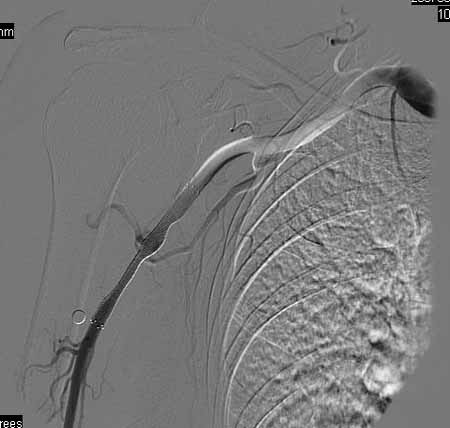

标题: DSA0091:肱动脉支架 [打印本页]

标题: DSA0091:肱动脉支架

女,66岁,右上肢无力.

图象清晰,做的很漂亮